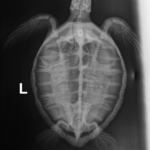

5.8 lb non-FP juvenile green

Moderate abrasions on the plastron and the carapace. Minor abrasions to the flippers and on the head. Possible, healed old hook wound in the right front flipper.